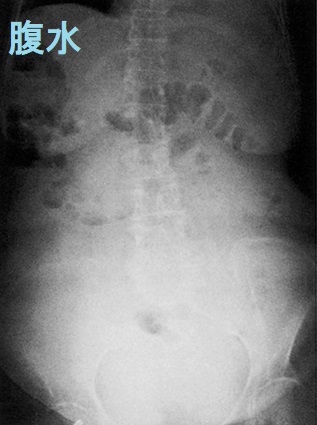

甲状腺機能低下症の4%未満に腹水(蛋白濃度が高い粘液水腫性腹水)。粘液水腫性腹水自体が腹膜を刺激し、卵巣癌の腫瘍マーカーCA125 の産生を増加させる。甲状腺ホルモン(チラーヂンS)補充療法により腹水は消失し、約1カ月遅れてCA125も正常値に。特に甲状腺ホルモン値(FT4,FT3)が低いと粘液水腫性腹水(腹水穿刺・利尿剤に反応悪く改善に時間を要す)・胸水(利尿剤で速やかに消失)・心嚢液(肺水腫、呼吸困難、右心不全、陰嚢・両下腿浮腫)貯留、腸管浮腫[甲状腺ホルモン剤(チラーヂンS)吸収障害]が出現。甲状腺乳頭癌、甲状腺未分化癌の腹膜播種がある。

甲状腺機能低下症で、特に血中の甲状腺ホルモン値(FT4,FT3)が低いと、粘液水腫による腹水・胸水・心嚢液が貯留し易くなります。

- 腹水は腹水穿刺・利尿剤投与にあまり反応せず、 改善に時間を要します